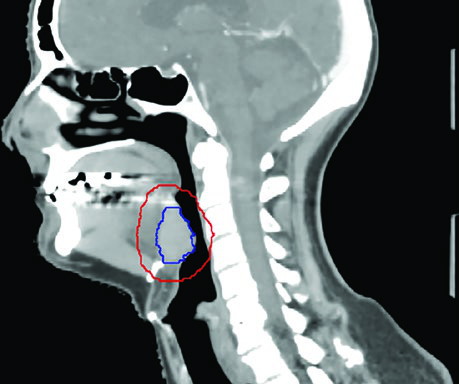

El caso de base de lengua VPH-positivo cT4N1 ilustra la cobertura hasta la base del cráneo en el lado N-positivo y la extensión del CTV para considerar cobertura bilateral del nivel IB cuando el tumor cruza la línea media. La vista sagital demuestra con particular claridad la importancia de la cobertura del espacio preepiglótico en tumores de base de lengua — un área frecuentemente subestimada por planificadores menos experimentados.